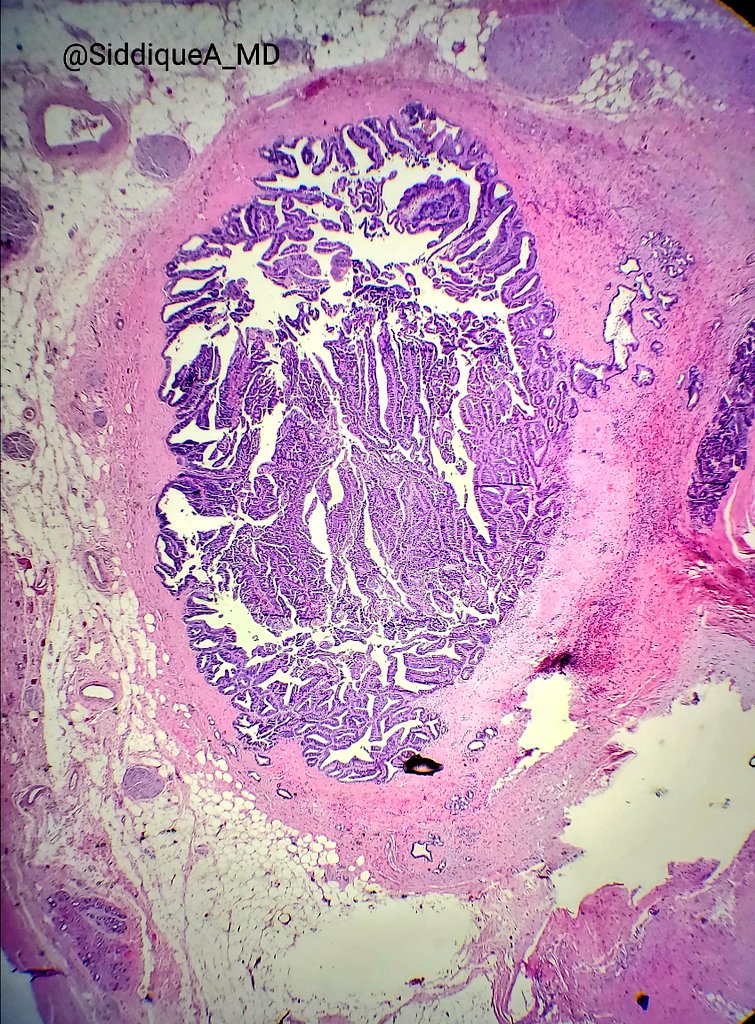

I'm obsessed with papillary lesions of the pancreatobiliary tract these days :D beautiful case of intraductal papillary neoplasm of cbd. No invasion.

#gipath#papillary#biliary pic.twitter.com/p2O4dNwp2J

Prikaži ovu nit -